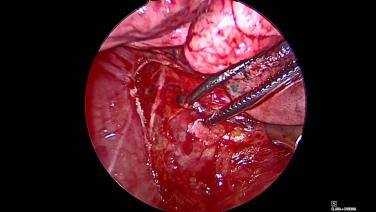

Thorascopic Lobectomy - Staple and Divide the Pulmonary Vein